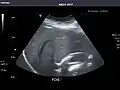

Left kidney -

Kidneys: Right and left kidneys measure 11.5 cm and 12 cm in length respectively. No hydronephrosis. Small left lower pole kidney cyst.